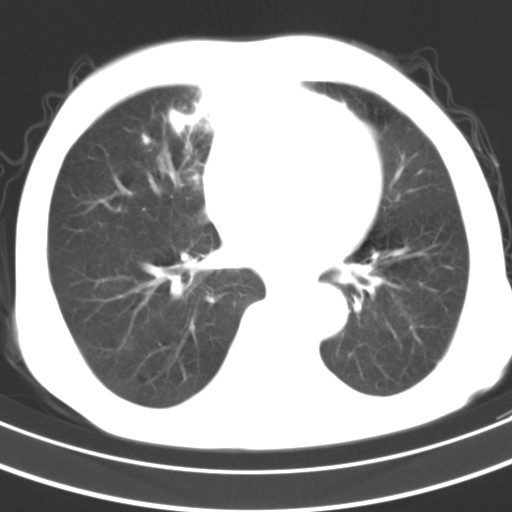

标题: CT18248:男,71岁,糖尿病住院,无发热、咳嗽、咳痰。 [打印本页]

男,71岁,糖尿病住院,无发热、咳嗽、咳痰。

1)两肺感染性病变(结核可能性大)。2)左肺上叶近纵隔胸膜下肺大泡。

1)两肺继发性结核。2)左肺上叶近纵隔胸膜下肺大泡。

两肺感染性病变(结核可能性大);左肺上叶近纵隔胸膜下肺大泡。